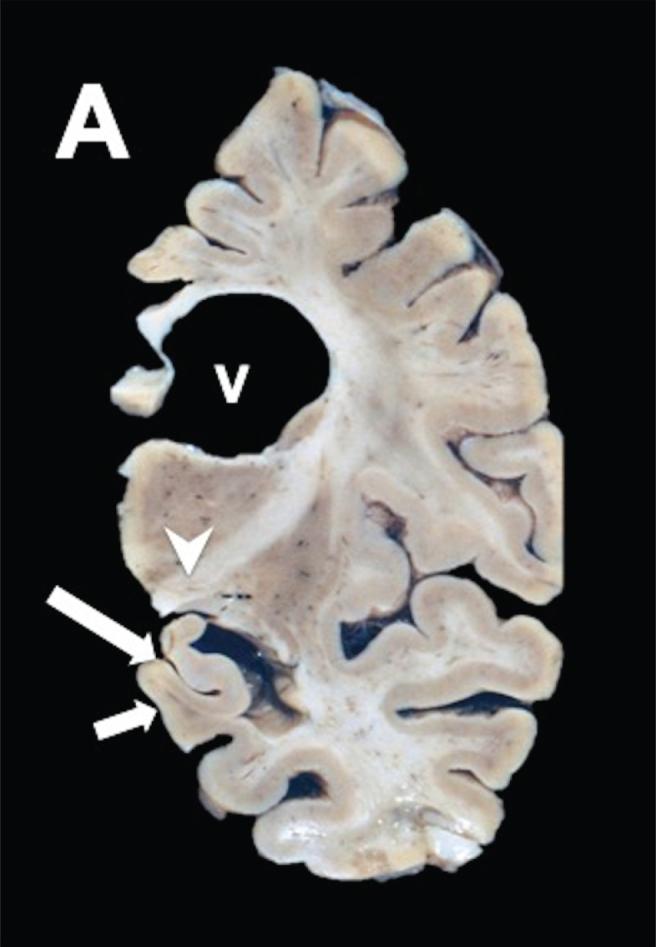

Molecular Processing of Tau Protein in Progressive Supranuclear Palsy: Neuronal and Glial Degeneration.

Alzheimer's disease (AD) and progressive supranuclear palsy (PSP) are examples of neurodegenerative diseases, characterized by abnormal tau inclusions, that are called tauopathies. AD is characterized by highly insoluble paired helical filaments (PHFs) composed of tau with abnormal post-translational modifications. PSP is a neurodegenerative disease with pathological and clinical heterogeneity. There are six tau isoforms expressed in the adult human brain, with repeated microtubule-binding domains of three (3R) or four (4R) repeats. In AD, the 4R:3R ratio is 1:1. In PSP, the 4R isoform predominates. The lesions in PSP brains contain phosphorylated tau aggregates in both neurons and glial cells.

Our results showed that PSP was characterized by phosphorylated tau in neurofibrillary tangles (NFTs) and glial cells. Tau truncated at either Glu391 or Asp421 was not observed. Extracellular NFTs (eNFTs) and glial cells in PSP exhibited a strong affinity for TR in the absence of intact or phosphorylated tau.